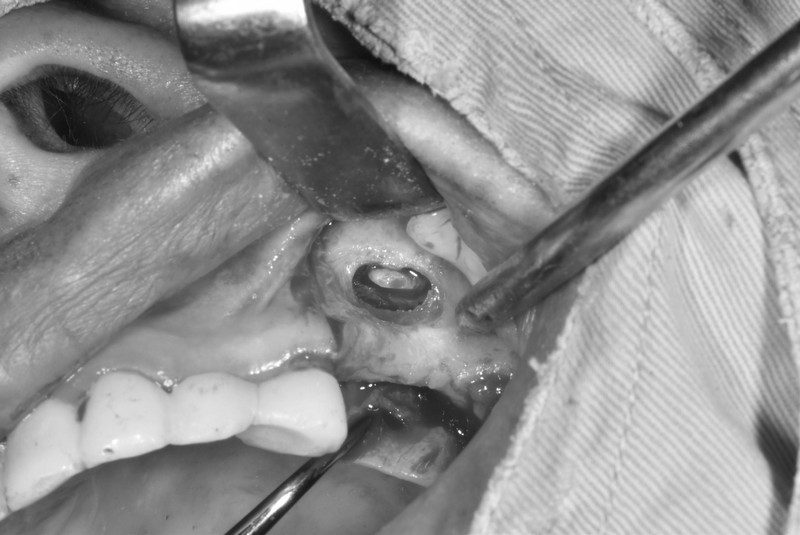

齒槽骨再生術(補骨)